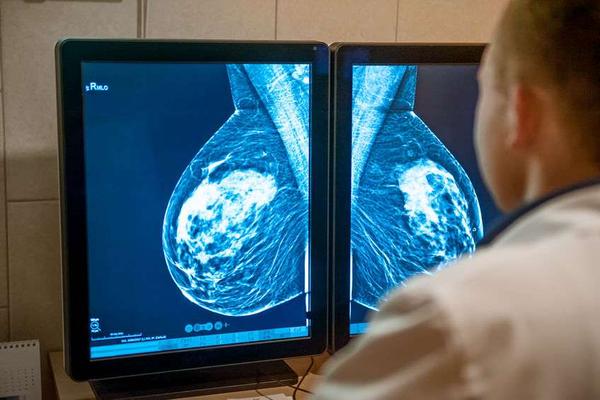

相关数据调查显示 , 乳腺癌是我国女性最为高发的恶性肿瘤 , 也是全球第一大恶性肿瘤!

所谓乳腺癌 , 指的就是出现在乳腺上皮组织内的细胞DNA变异 , 这些变异的细胞持续恶性单克隆增殖 , 最终形成了肿瘤 。

如果患者能在早期发现乳腺癌 , 并积极进行手术切除治疗、配合后续治疗 , 患者五年内的生存率甚至是能高达90%以上 , 且有望实现临床治愈 。因此 , 对女性而言多了解一些乳腺癌相关症状很有必要 。 在临床看来 , 乳腺癌病发且在病情发展期 , 最为典型的症状就是以下几个!

1、乳腺肿块:乳腺肿块为乳腺癌最常见的临床表现 , 有近90%的乳腺癌患者初次就诊 , 就是因为无意间触摸到了异常的肿块 。